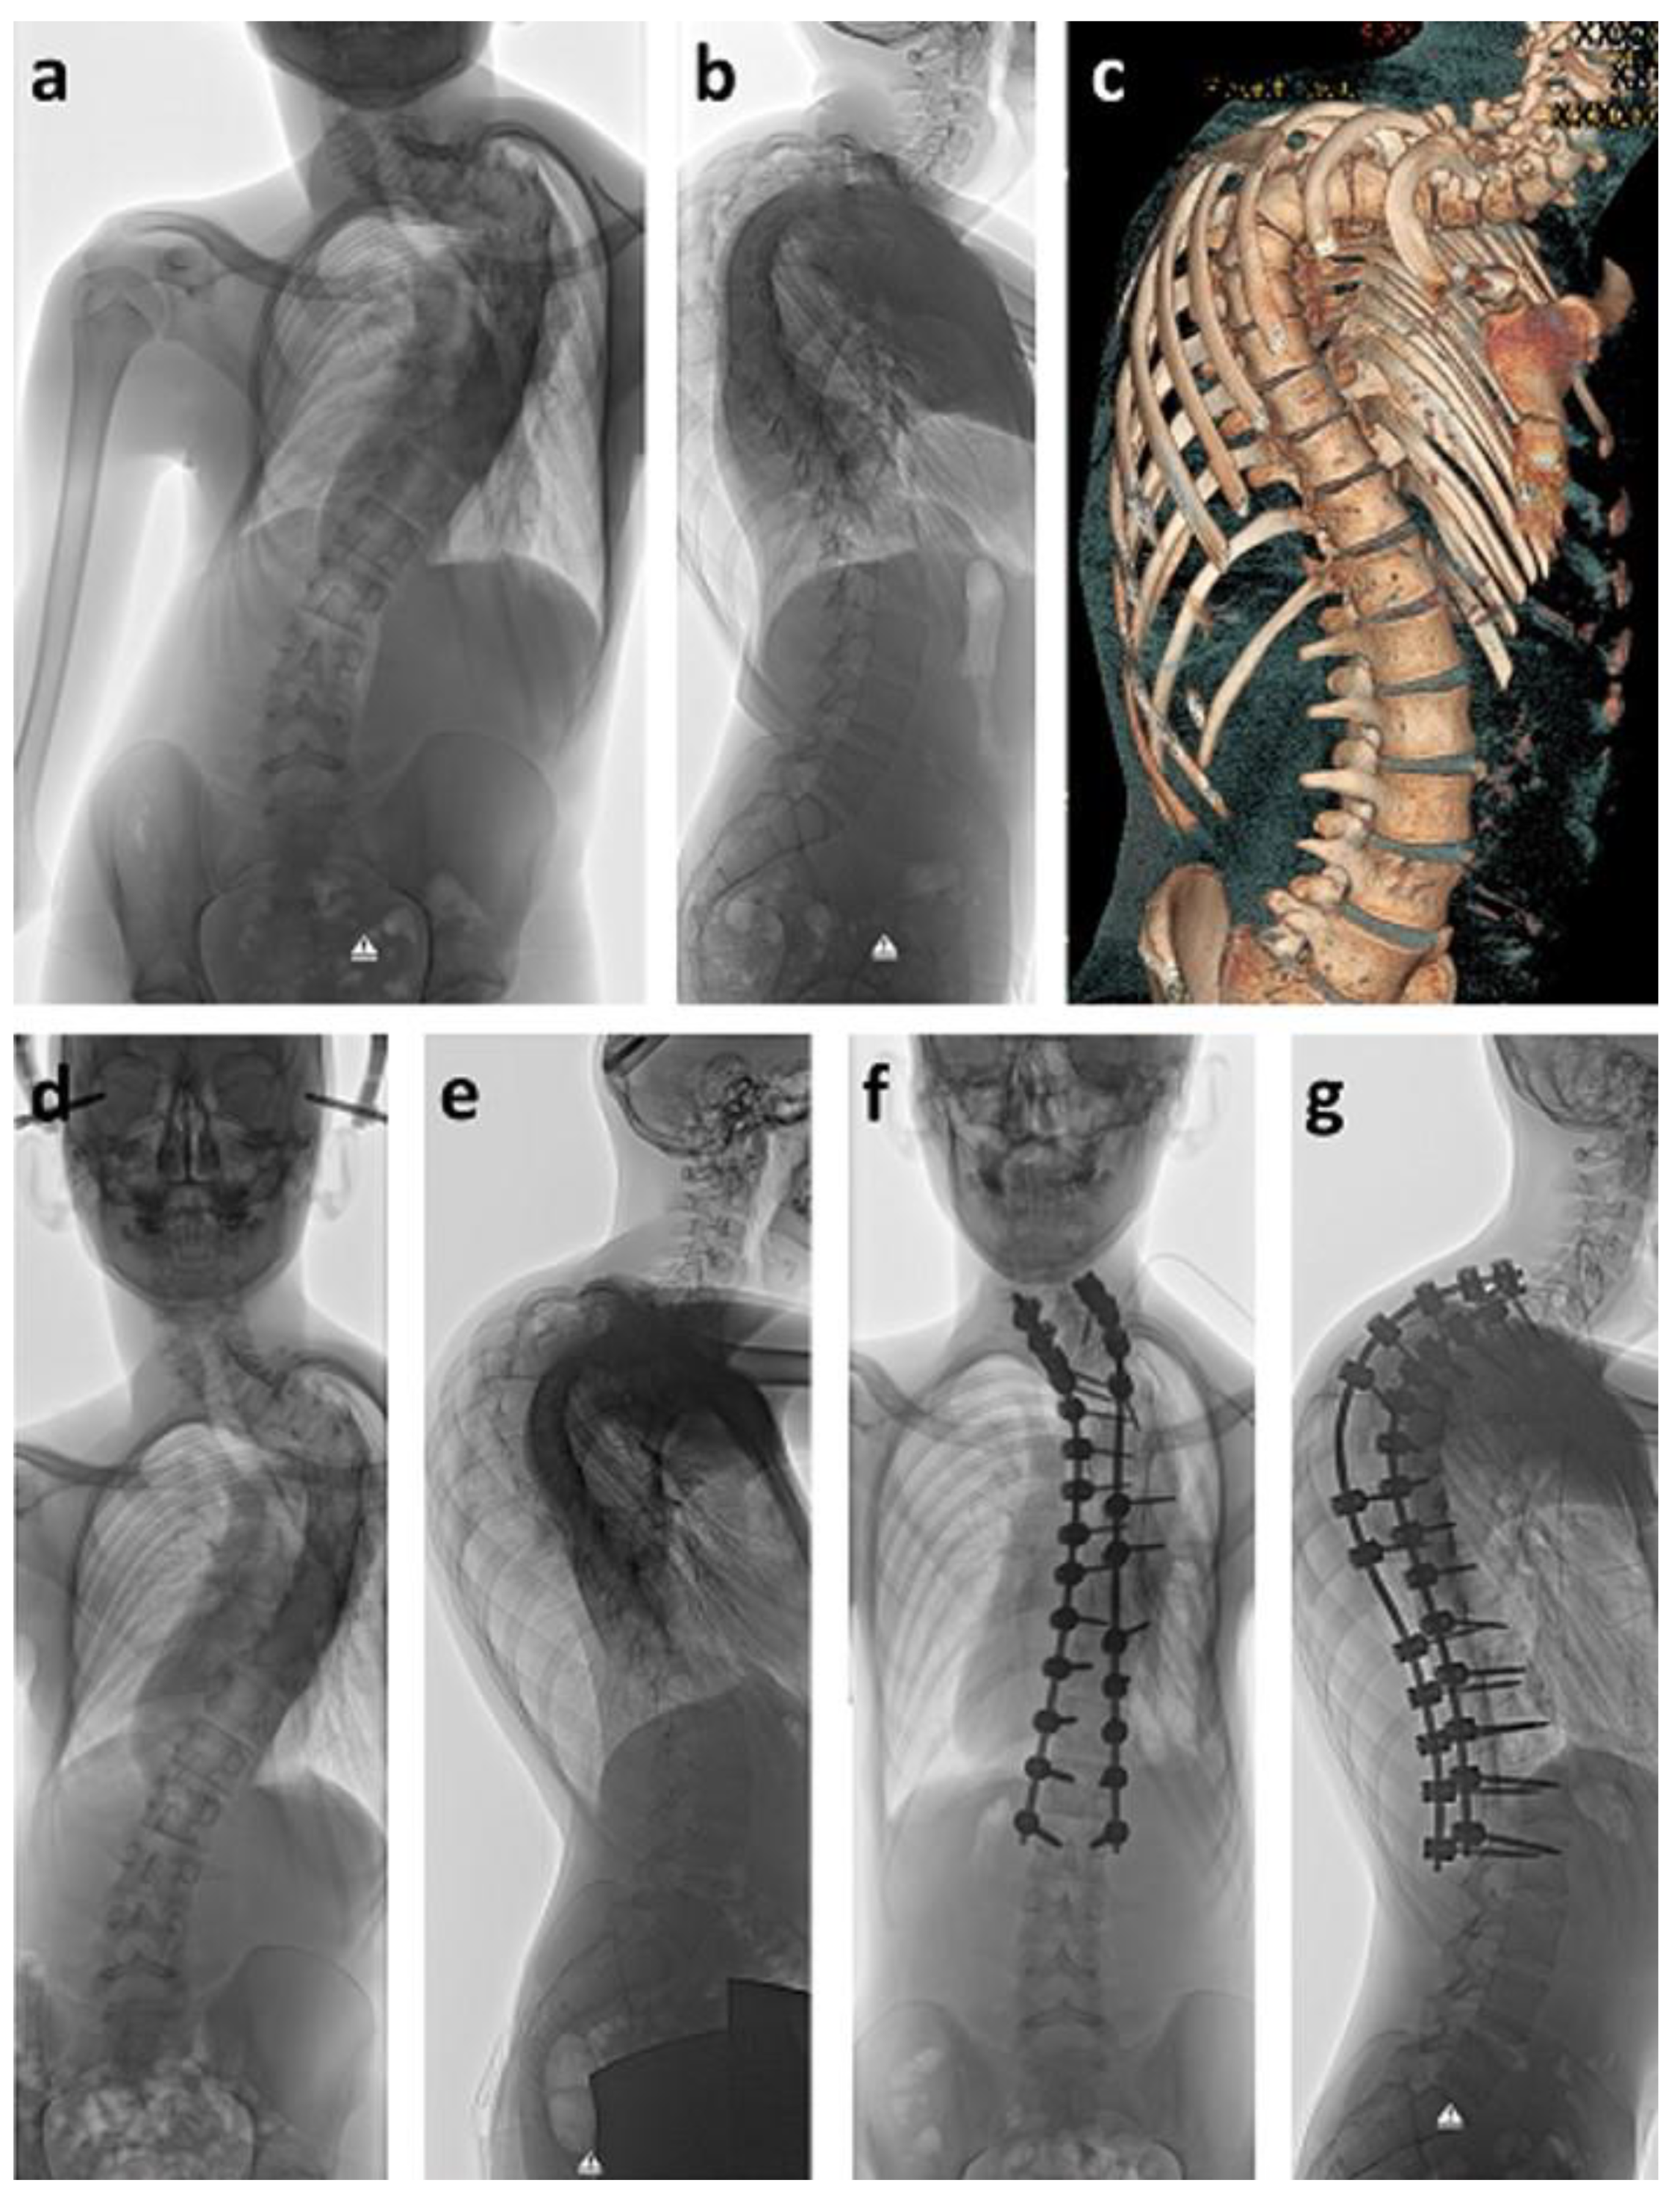

Figure 2. Seven-year old girl with neurofibromatosis type I and scoliosis of 101° (a,b). Bilateral rib-to-pelvis vertical expandable prosthetic titanium rib (VEPTR) devices were able to correct the scoliotic deformity to 43° (c,d). VEPTR implants are surgically lengthened every six months (e,f) to maintain the correction and to permit growth.

Surgical deformity correction was performed with bilateral VEPTR devices implanted in children ten years or younger. Using this technique, nine cases were treated and received an average of nine lengthening procedures every six months so far. As a result, the scoliotic curve was significantly (p < 0.001) corrected from an average of 83° to 49° (41%) directly after surgical implantation (Figure 2). Kyphosis significantly (p = 0.0133) improved from 60° to 38°, whereas lordosis remained stable at 32°. A careful evaluation of CNS structures was performed prior to surgical spinal deformity correction. This included MRI, neurosurgical evaluation, and analysis of evoked potentials in order to evaluate the risk of neurological complications. There was no neurological deterioration in the treated group.

Many studies have proven the efficiency of several growth-friendly spinal implants with various fixation and distraction methods to control spinal deformity and allow thoracic growth [26,27,28]. Bilateral rib-to-pelvis VEPTR constructs have the advantage of leaving the spine untouched as well as being expanded without the use of magnetic components, thus allowing MRI examinations after device implantation [10]. In our study, nine skeletally immature patients received VEPTR treatment with an average deformity correction of 41% after initial implantation, which lies within the range of 29–41% correction as reported in other studies [11,12,27]. A small group of paraplegic children with intraspinal tumors who were treated with bilateral growth-friendly spinal implants had been previously analyzed and compared to neuromuscular patients by our study group [11]. Even though these patient numbers are small, a significant initial curve correction constantly showed more severe curve progression over time in the tumor group and less favorable pelvic obliquity control [11].